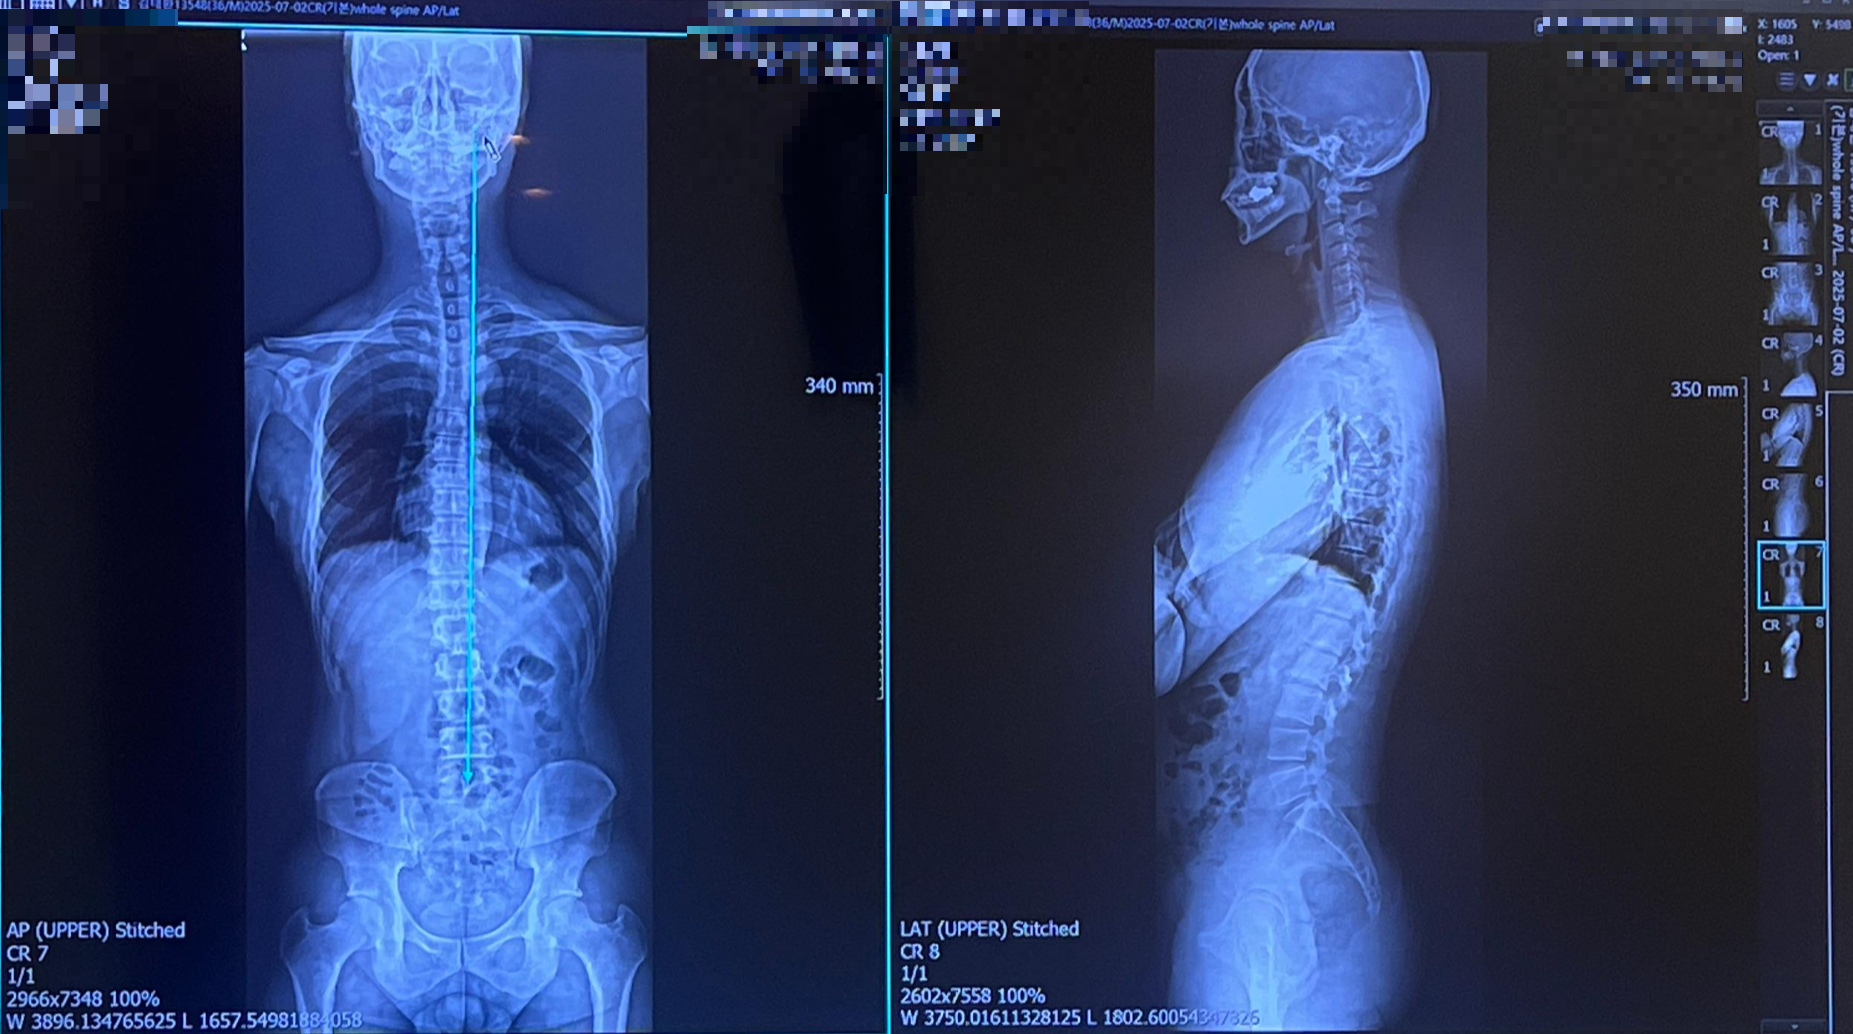

최근 목 통증 때문에 병원을 찾았다가 큰 깨달음을 얻게 되었습니다. 단순히 목에 담이 걸린 줄 알았는데, 정형외과에서 정밀 촬영한 X-ray 결과를 보고 충격을 받았죠. 제 목뼈는 일자목(거북목) 상태였고, 심지어 오른쪽으로 기울어져 있었습니다.

의사 선생님 말씀으로는 이런 증상이 단순한 통증이 아니라 경추(목뼈) 구조와 디스크의 문제에서 비롯되었을 가능성이 높다고 하더군요. 치료를 위해 도수치료도 받았지만, 결국 가장 중요한 건 평소의 자세라는 조언을 들었습니다.